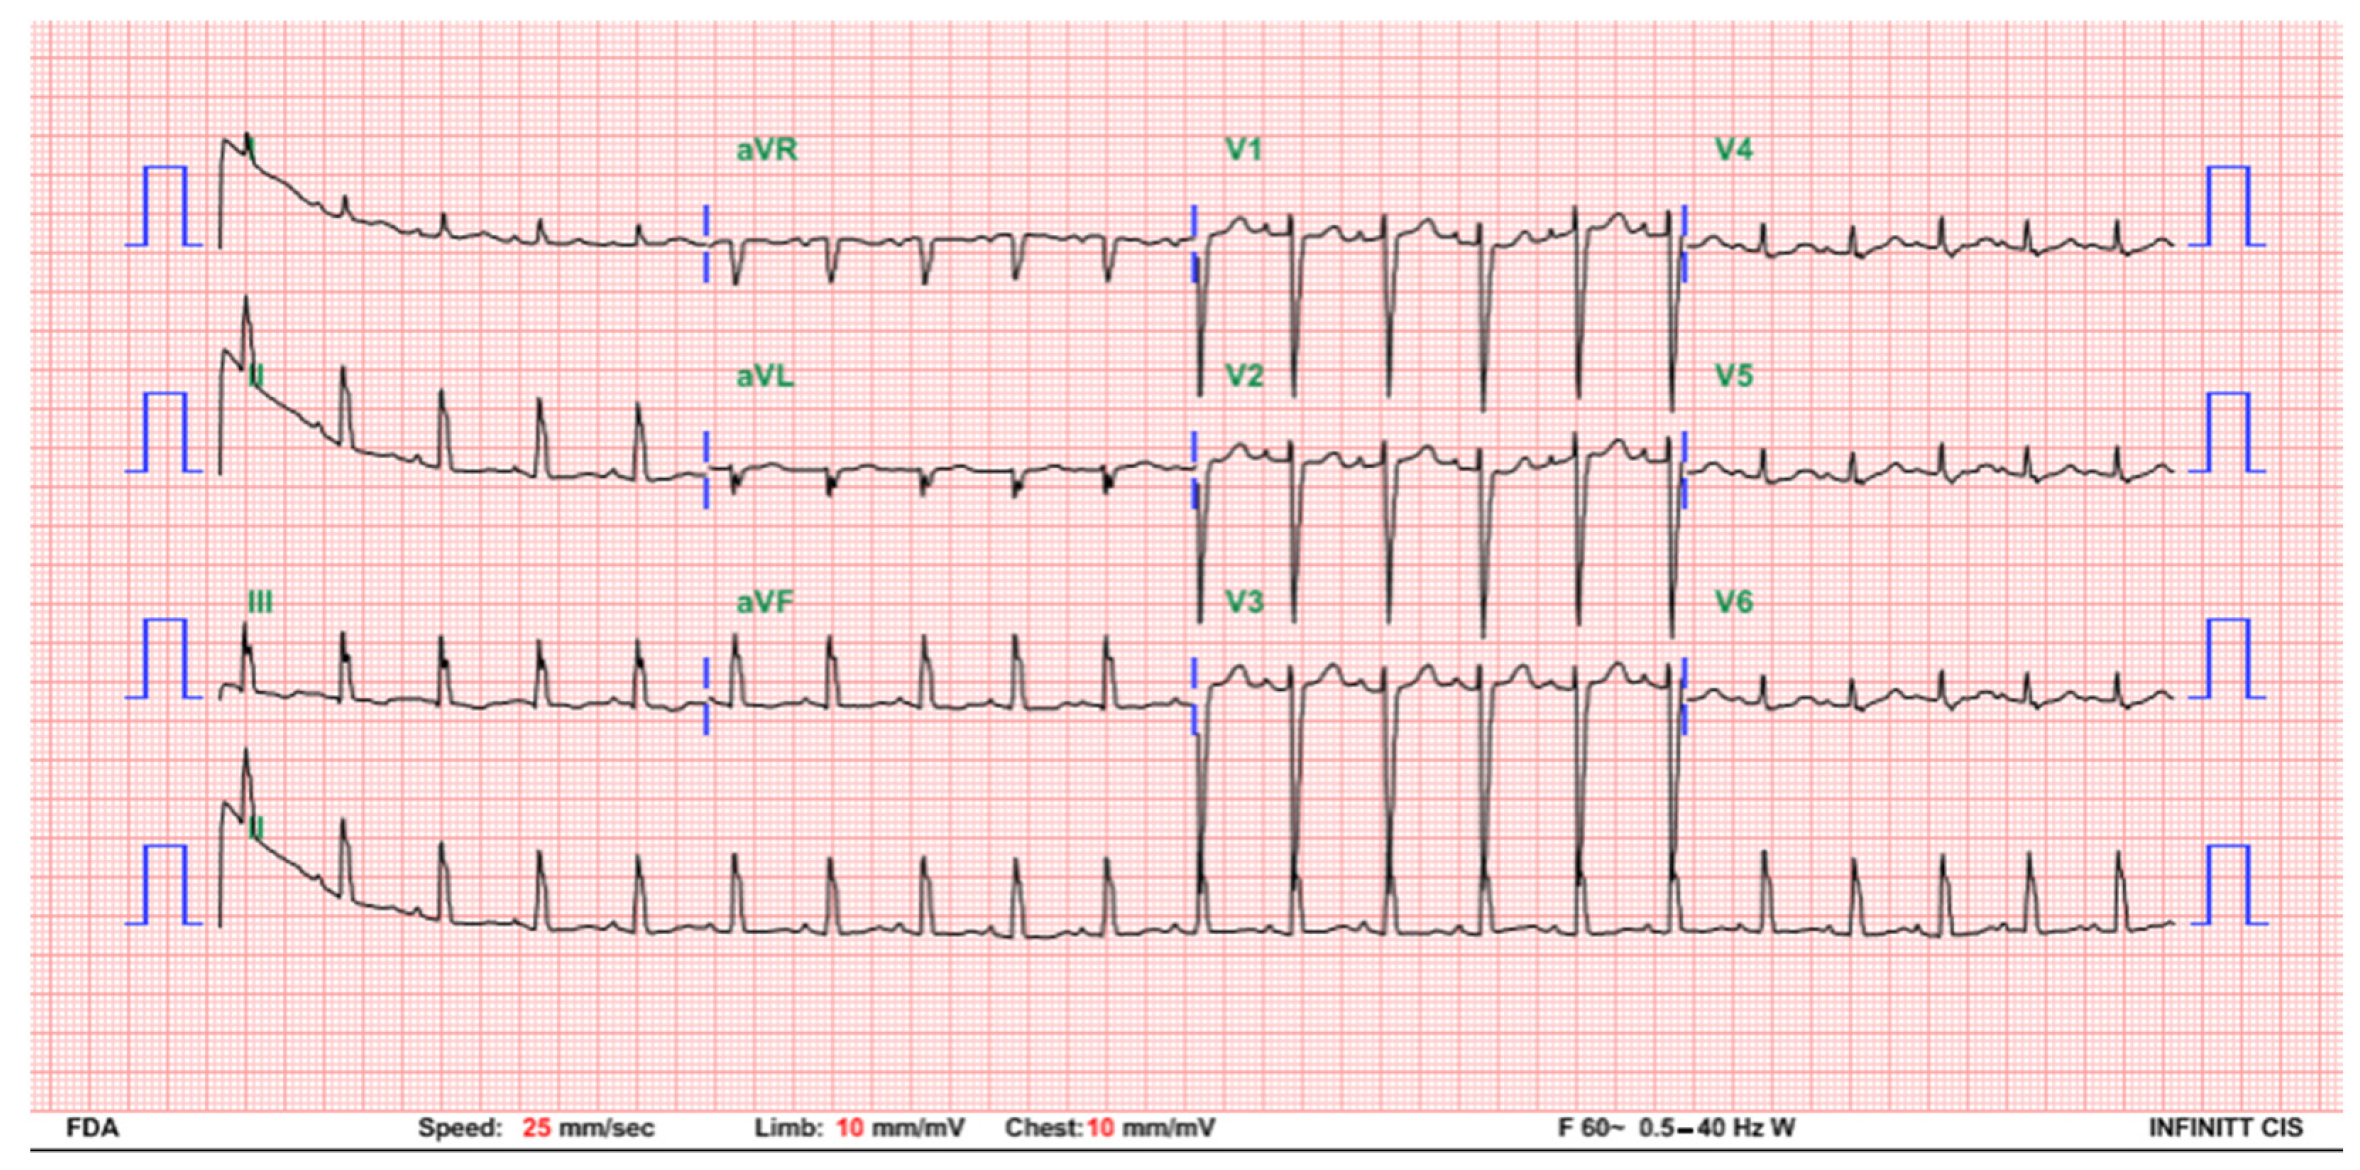

2. Case Presentation